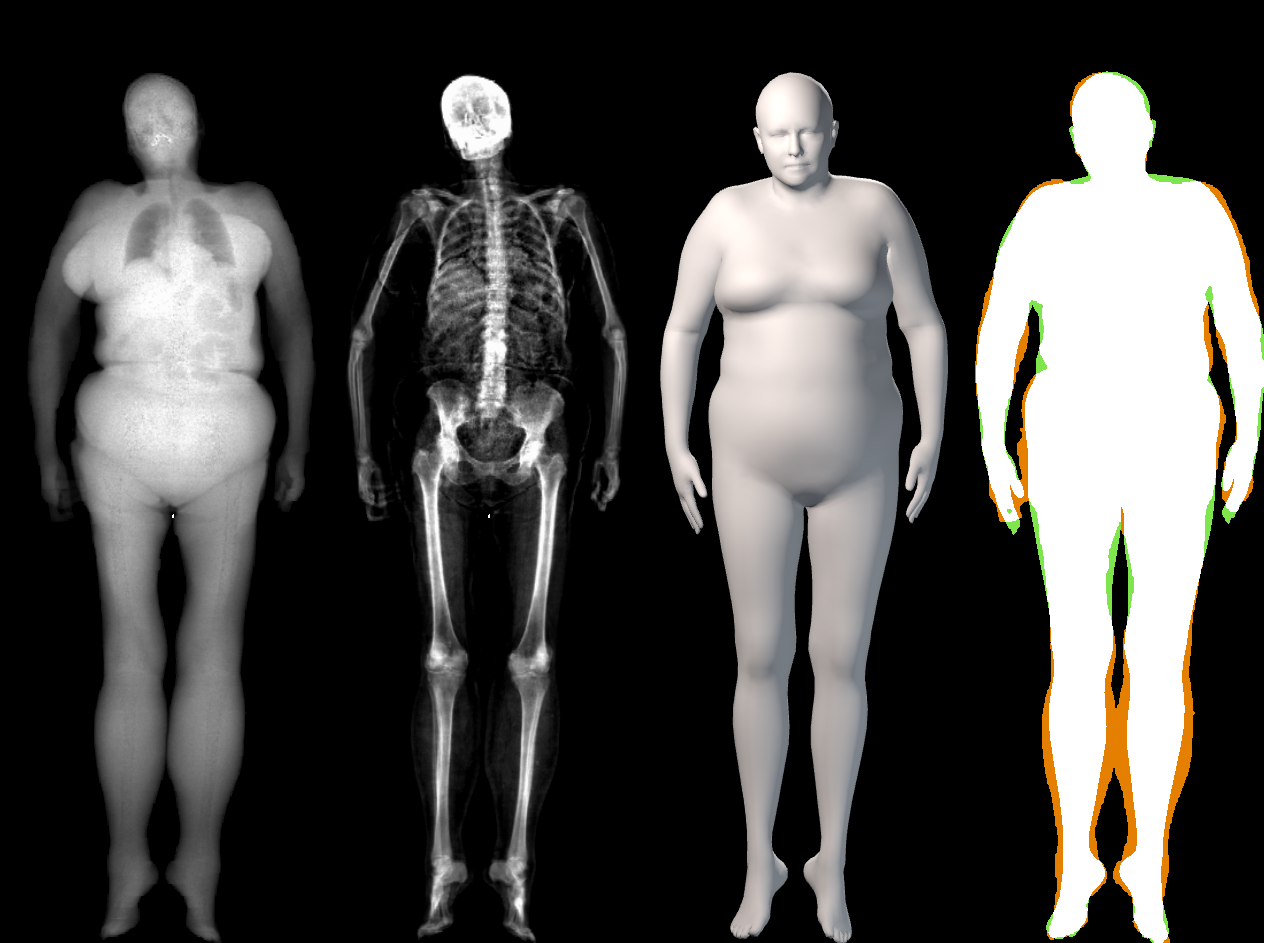

The key problem, however, is obtaining training data that simultaneously gives the inside and outside of the body in 3D. Most imaging technologies that simultaneously capture the inside and outside of the body use ionizing radiation, which is harmful to humans; e.g. Computed Tomography (CT) and X-rays. This means that such data is extremely limited, preventing learning-based methods. Our insight is to use dual-energy X-ray absorptiometry (DXA) data. DXA scans use low-dose X-rays to measure bone mineral density and body fat composition. The radiation level is so low that it is certified to be used on healthy patients for clinical studies, such as the UK Biobank [36]. In a DXA scan, two images are computed by combining two different energy levels: a soft-tissue image and a bone image (Fig. 2). In the silhouette of the body can clearly be seen, whereas reveals the structure and shape of the bones.

From the input images (, ), we compute the corresponding skin and skeleton segmentation masks (, ). For the skin mask , we threshold . As some small artifacts remain, mainly due to pixels in the lungs with low intensity values, we detect the closed contours on the image and fill in small areas. In Fig. 2 we show pairs of input and the obtained mask .

In our work, we use a simple heuristic to automatically segment the bone tissue in the bone images: we assume that the brightest pixels in each image belong to bone tissue. We empirically set for the male DXAs and for the female. As small artifacts remain (earrings, clothing, etc.), we remove small connected components with an area less than 50 pixels. Note that we do not claim to segment all bone tissues in the DXA images. While our segmentations are coarse, they capture the structure and location of the bones inside the body (as shown in Fig. 2); this is what we need to fit a 3D skeleton to them.

The presented metric has a limitation: predicting all the skin volume as bone would obtain a perfect result (, ). In Fig. 4 and Sup. Mat. we show that visually, OSSO’s predictions are coherent and match the DXA bone images better than Anatomy Transfer. In Sup. Mat. we provide examples of subjects with high Body Mass Index, for which Anatomy Transfer predicts a stretched skeleton, while ours are closer to the DXA skeleton mask.

In this section we illustrate the alignment results of the STAR model on the DXA images. Those alignments were obtained with the optimization presented in Sec. 3.3 of the main paper. These results complement the quantitative evaluation reported in Sec. 5.1 of the main manuscript, where the intersection over union coefficient between the DXA mask and the computed skin silhouette is for females and for males. In Figure 14, we show the qualitative results. The color-coded images show that the skin registrations faithfully capture the DXA skin silhouettes.